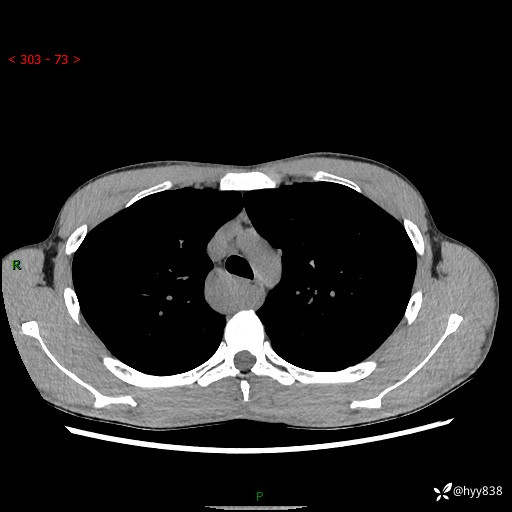

年轻男性,发现后纵隔占位1周余。征象简单,难在定位---结果公布~

现病史:患者于1周前体检行检查发现后纵隔占位,患者平素无明显咳嗽咳痰,无心慌、胸闷、胸痛、呼吸困难、低热、盗汗,无头痛、头晕,无腹痛、腹胀等不适。现患者欲求进一步治疗,遂来我院就诊,以“纵隔占位”收入我科。 患者自起病以来,精神可,睡眠可,饮食可,大小便正常,体重无明显改变。

胸部CT平扫+增强